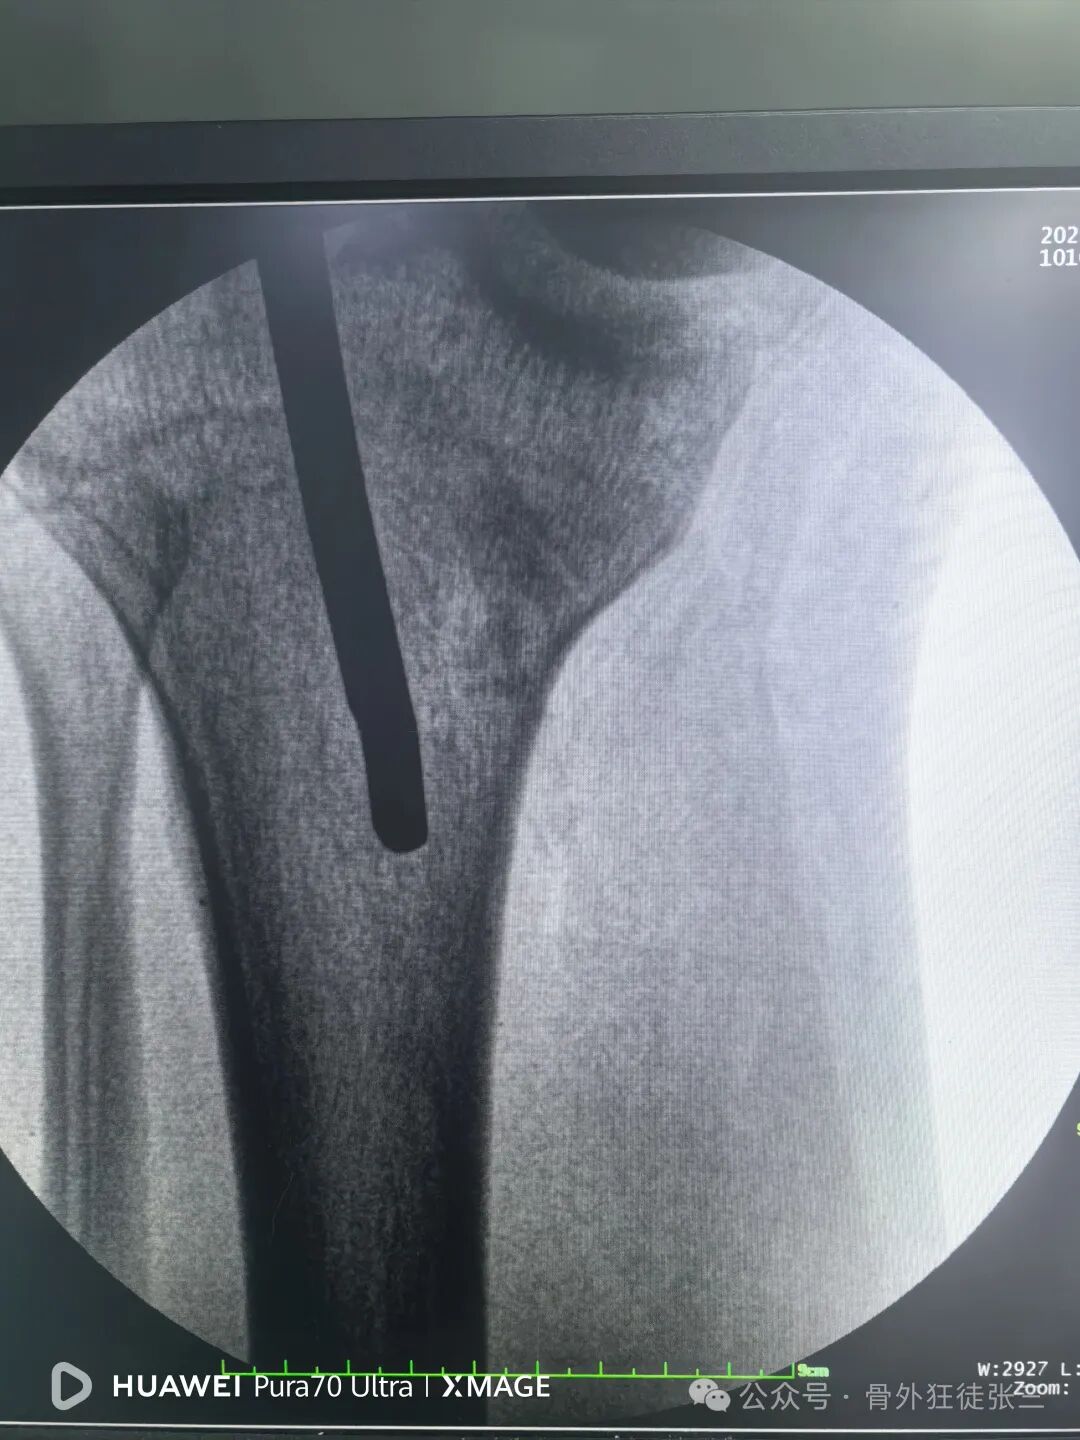

踝关节侧位钉子长度满意,居中

6,扩髓时,不需要复位,但是需要扩到过狭窄部位,不要一杆子扩到底,容易不居中。

7,髓内钉本身就是复位工具,在此时依靠髓内钉+手法,几乎都能顺利复位。